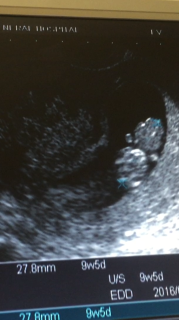

9週5日のエコーです。 赤ちゃんは27ミリにまで成長しました。 心拍もリズム良く動いています。 頭や胴体がはっきりしてきました。 画像として子供が見れると、とても安心します。ママはどんなに辛くても頑張りますので、どうか、元気に大きくなって下さい